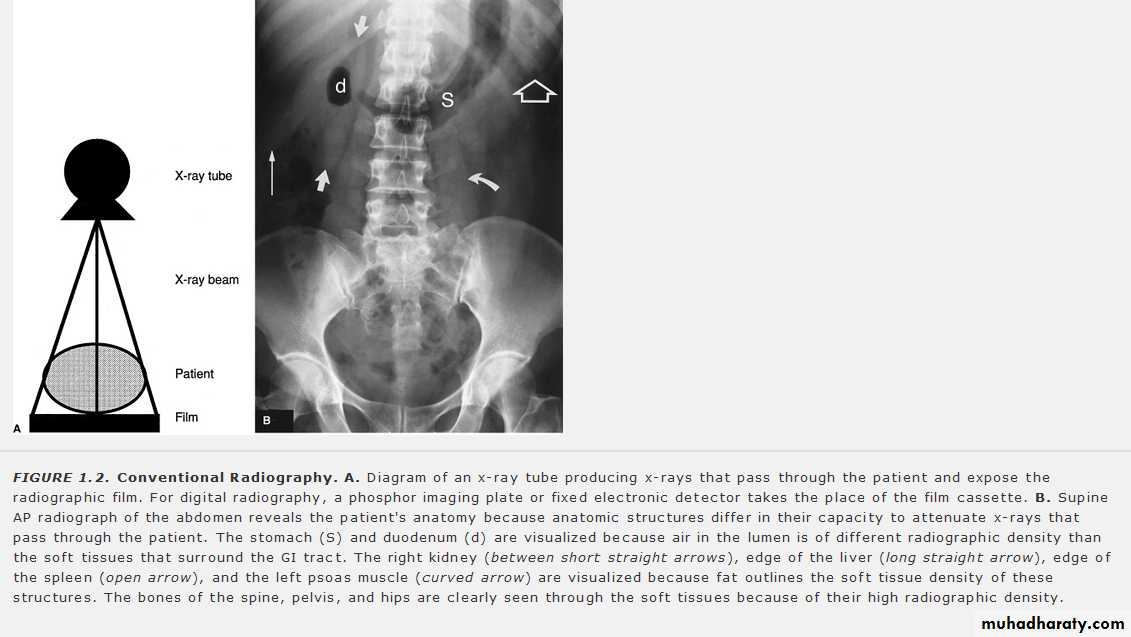

X- RAY GENERATIONX-rays are generated in an X-ray tube, which consists of a vacuum tube with a cathode (tungsten filament ) and an anode (tungsten target) .

The x-ray beam is produced by bombarding a tungsten target with an electron beam within an x-ray tube .

According to x- ray attenuation in the tissues ( x – ray penetration) ,the radiographic appearace can be graded into :

Tranceradiant as gases

Radiolucent or trancelucent as in fatty tissue

Mild radio radio-opague as fluid , muscle ..

Moderate radio-opague as bones and calcifications

Dense radio-opague as metals and contrasts